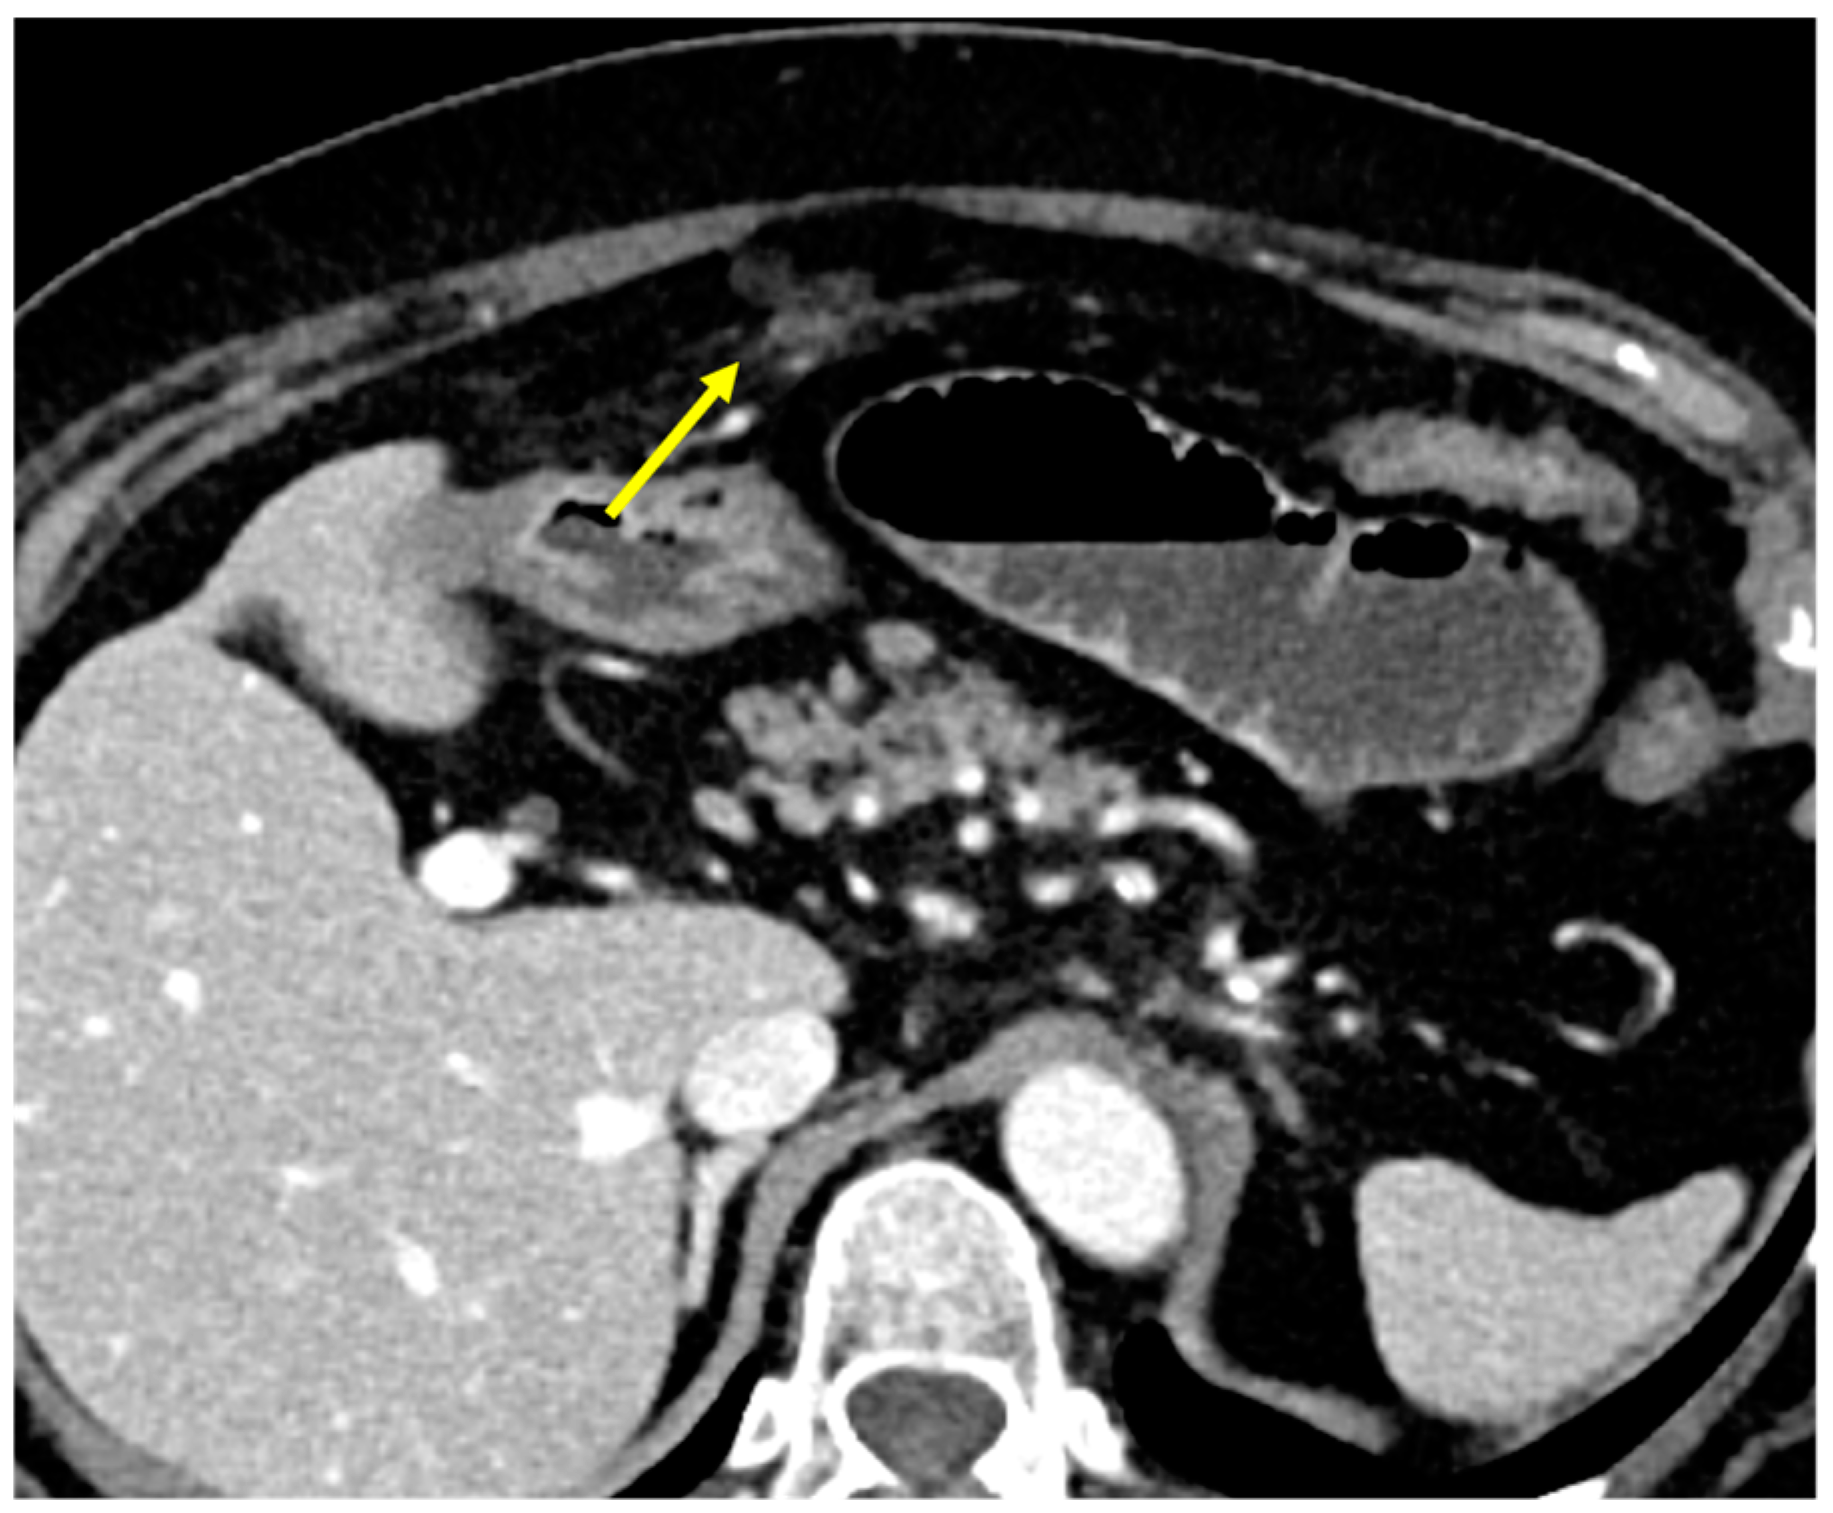

- Plaque pattern: confluent nodular plaques, typically involving the lower surface of the right diaphragm (Figure 3);